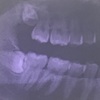

抜いたのは上右第一小臼歯と下右第二小臼歯。

上の前から4番目と下の前から5番目です。

来週も反対側の上下2本を抜歯するのですが、右側の方が奥の歯を抜くので目立たないということで、右の上下を抜いてきました。